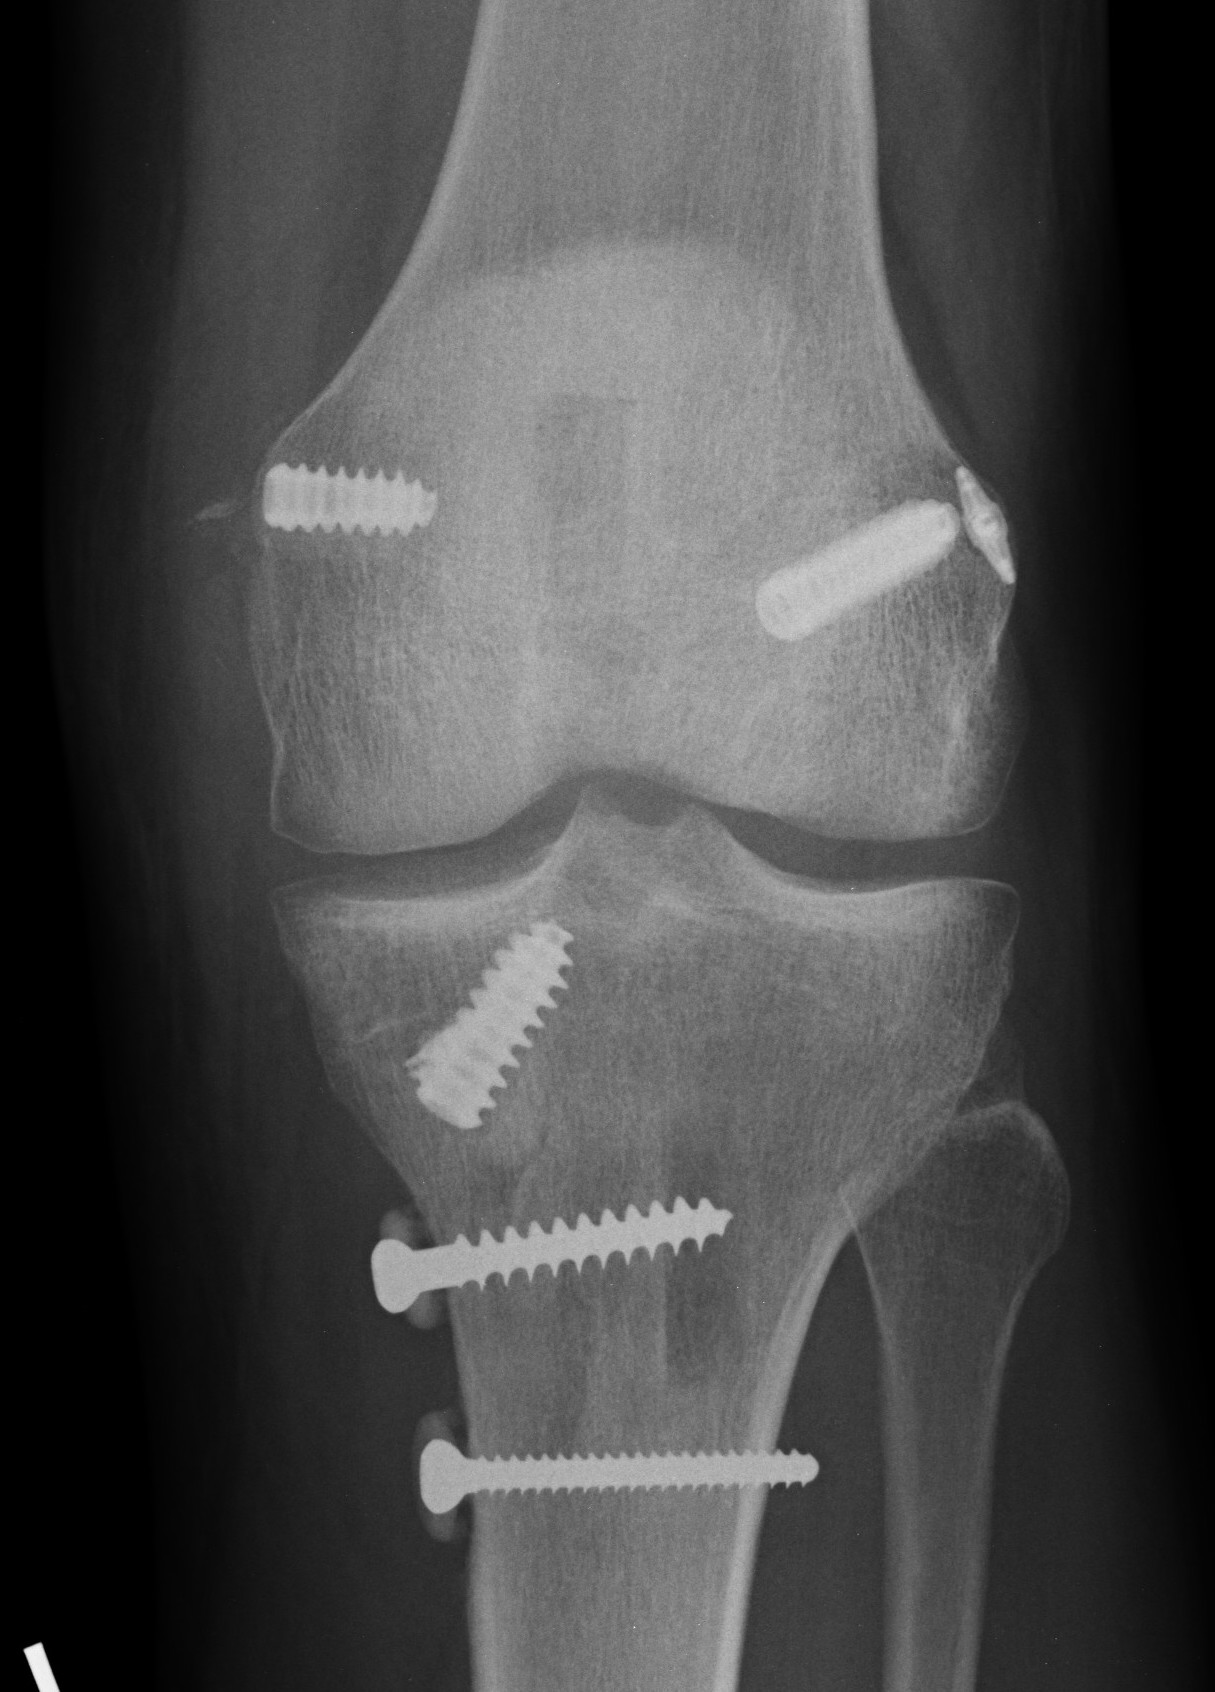

Xray following PCL reconstruction, LCL and politeus reconstruction. CT demonsrating popliteus and LCL tunnels